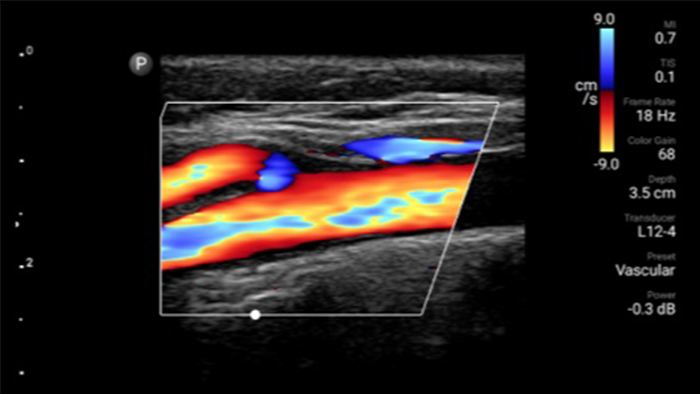

Disminuya las complicaciones de las inserciones de CVC

La guía por ultrasonido en tiempo real puede mejorar la precisión y la seguridad de las inserciones de CVC.

Transductor de matriz lineal de banda ancha Lumify L12-4

• Rango extendido de frecuencias de operación entre 12 y 4 MHz • Tamaño de apertura: 34 mm • 2D, Doppler orientable a color, Modalidad M, XRES avanzado e imágenes armónicas multivariables, SonoCT • Imágenes de alta resolución para aplicaciones superficiales: tejidos blandos, vasculares, superficiales, musculoesqueléticos y pulmonares • Marcador de línea central • Transductor USB-C con cable reemplazable